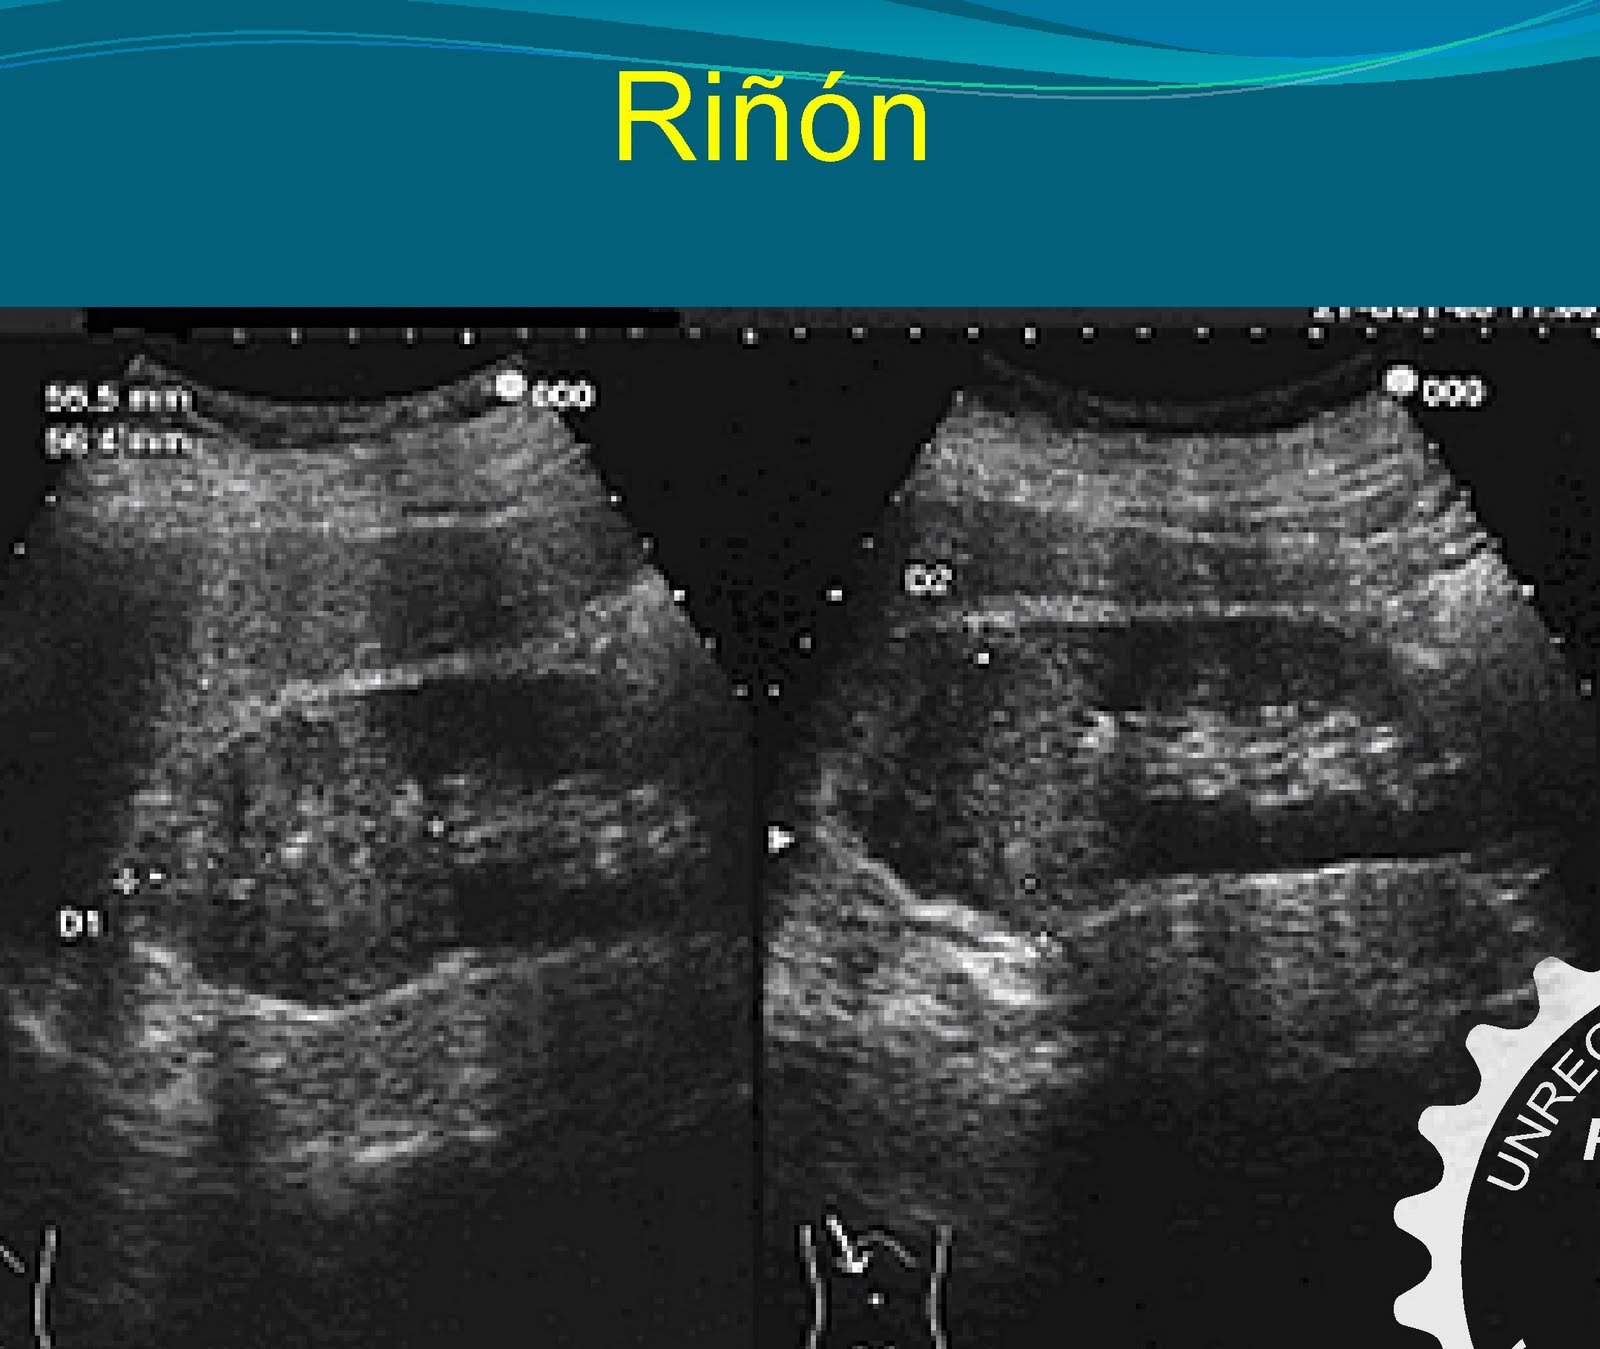

Diagnóstico Ecográfico en la Urgencia- Santojanni: Ecografía Renal

Source: ecoenlaurgenciasantojanni.blogspot.com 1600 x 1349

.